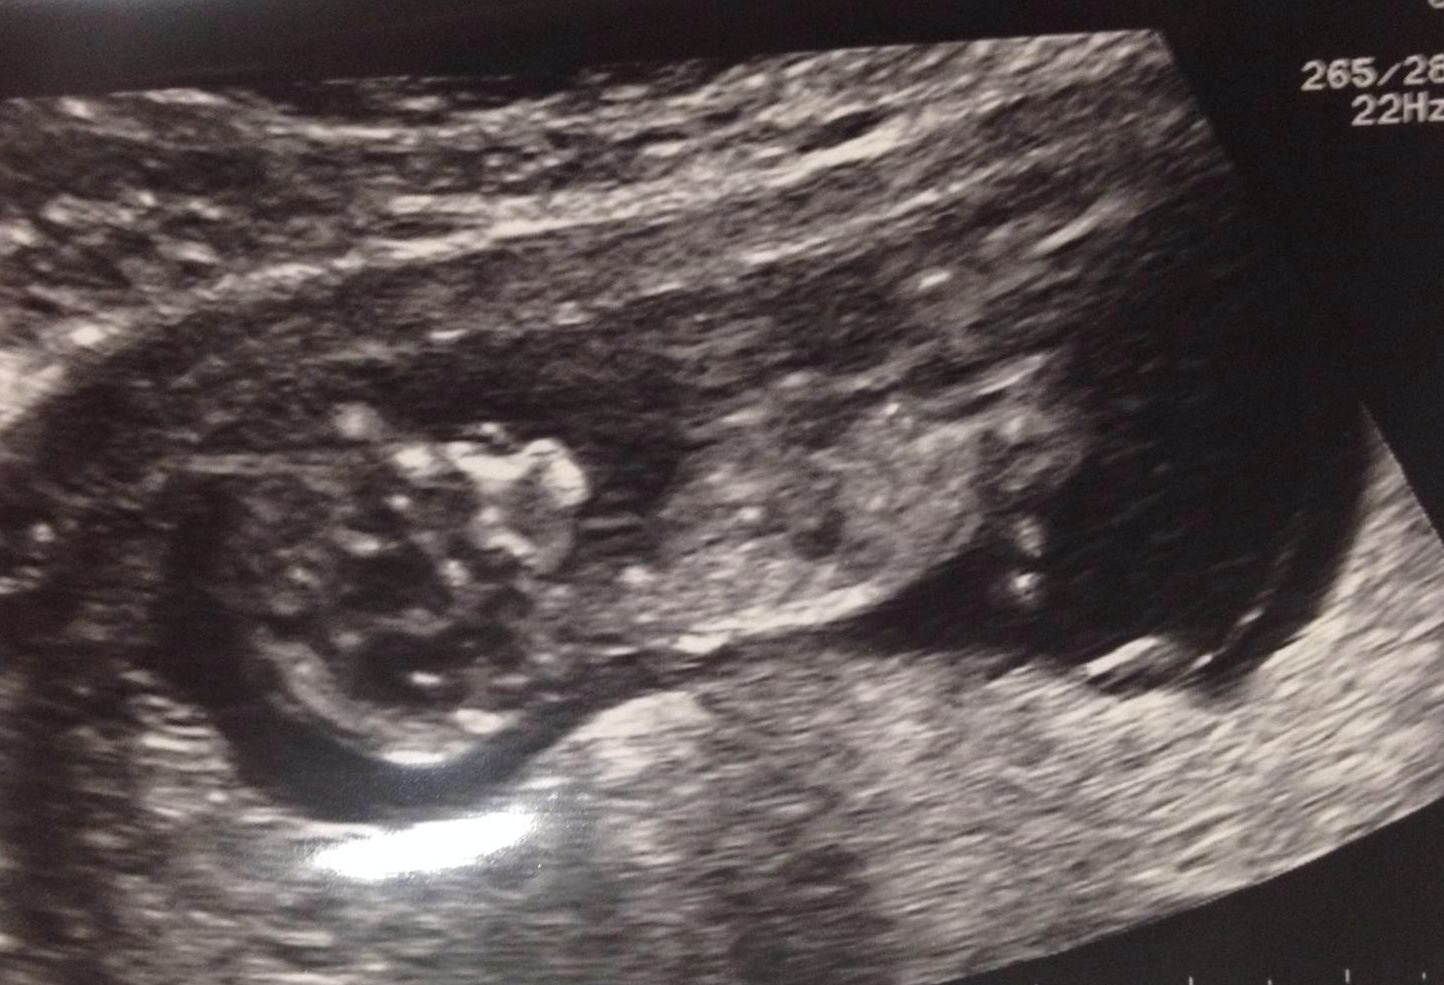

Cute but don't see a nub sorry

Can't see a nub either any more pics

If what im seeing is the nub, girl lean.